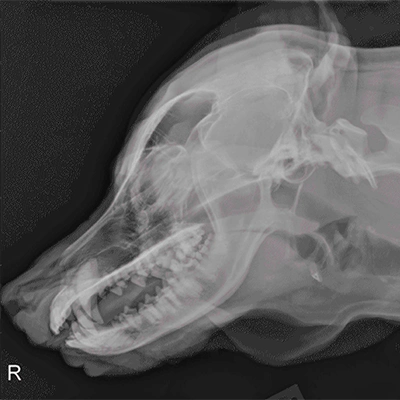

Rentgen (RTG)

Rentgen se používá hlavně k zobrazení kostí a jejich poškození, například při podezření na zlomeninu, vykloubení nebo jiné úrazy hlavy. Výhodou je, že je dostupný téměř na každé veterinární klinice, je levný a rychlý. Nevýhodou je, že špatně zobrazuje měkké tkáně a někdy je nutné zvíře složitě polohovat, což může ovlivnit kvalitu snímků.